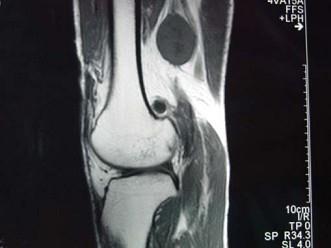

问题 男,48岁,腘窝上方疼痛2年余,呈持续性钝痛,且疼痛逐渐加重,曾以"结核”治疗无明显好转,体检腘窝上方肿胀,局部压痛,实验室检查均正常,请结合所提供的图像,选择最佳选项 ( )

选项 A、腘窝上方神经鞘瘤 B、腘窝上方脓肿 C、腘窝上方血管瘤 D、腘窝上方肌腱神经纤维瘤 E、腘窝上方囊肿

答案 D